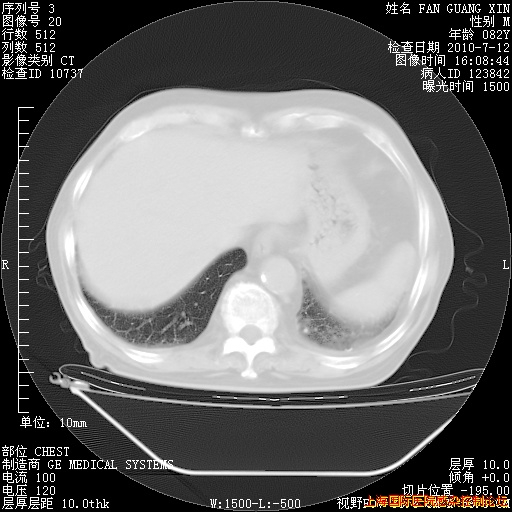

6月12日纵膈窗

回复

整整相隔30天的肺部CT好像有所好转啊。甲强龙减量第3天,需要观察体温。